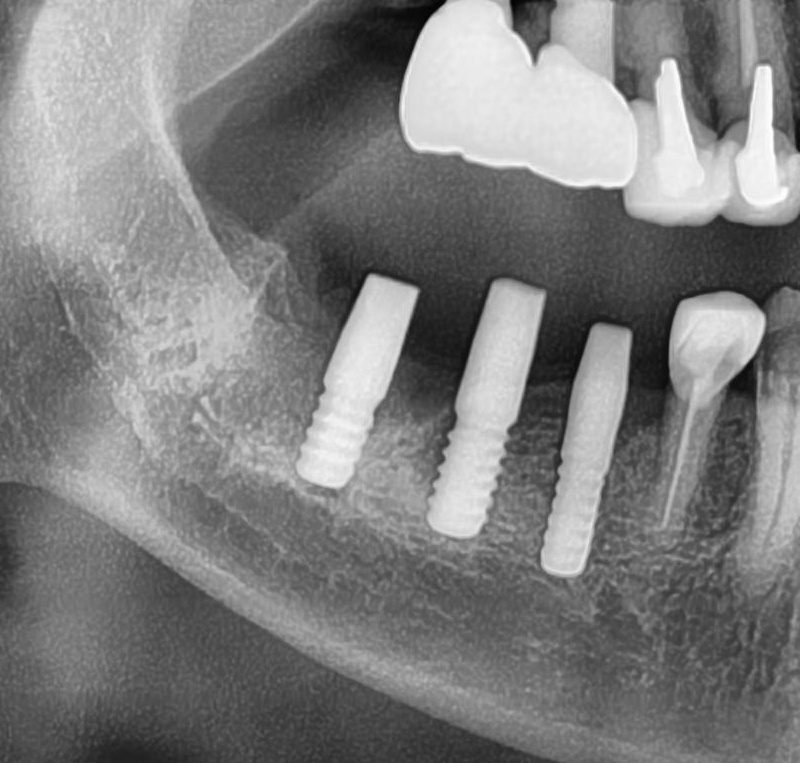

しっかりとインプラント埋め込まれた後は、動揺がないか、噛んだ時に当たらないかなどを確認して、最後にパノラマ写真を撮影して今回のオペは終了となりました。